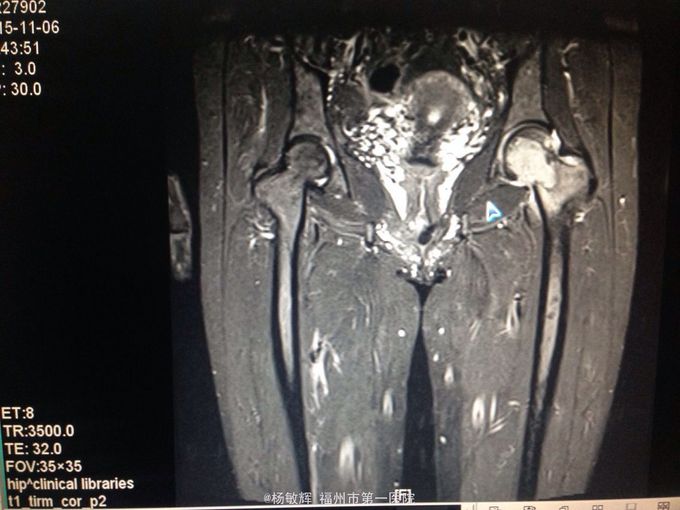

女性,48岁,以“左髋部疼痛伴活动受限2年”为主诉入院。缘于入院前2年无明显诱因出现左髋部疼痛不适,疼痛呈间歇刺痛,无向他处放射,伴左髋部活动受限,间歇性跛行,就诊当地医院查髋部X线提示:骨质破坏。MRI提示:左股骨头异常信号。当地医院诊断股骨头占位,未予以特殊处理,2周前疼痛加剧,就诊我院,查左髋部MRI提示:左髋部占位,骨巨细胞瘤可能性大。入院后于穿刺活检送病理,病理结果:左股骨头骨巨细胞瘤。拟:左股骨近段骨巨细胞瘤,收住院。

左股骨近段骨巨细胞瘤 入院后完善相关术前检查,未见明显手术禁忌症,行:左股骨近段占位切除+人工髋关节置换术